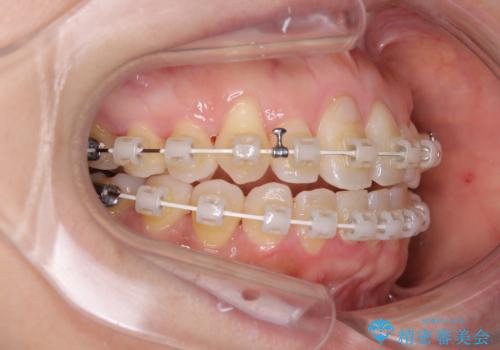

- 審美装置

- 2年1ヶ月

下顎骨が左側にズレて成長してしまったため、左側の咬み合わせが上下反対になっている状態でした。

そこまでの処置は望んでいらっしゃらなかったため、歯列矯正でのカムフラージュにより咬み合わせを改善することとしました。

予想通り左側の咬み合わせの調整に苦労をしましたが、最終的には違和感のない咬み合わせを達成することができました。